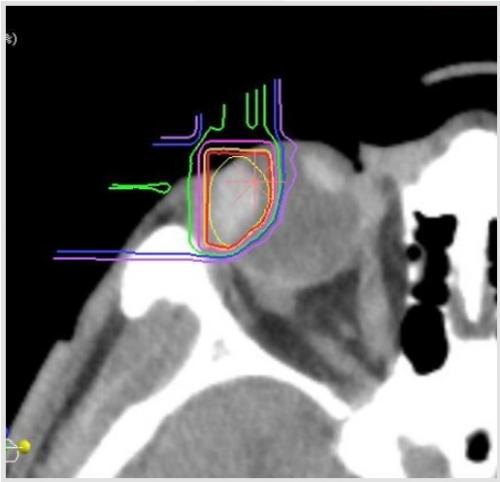

当院においても2001年より眼球脈絡膜悪性黒色腫に対する治療を、重粒子線を用いて施行しており(図1)、局所制御率93%、5年生存率80%と良好な成績が得られています※3。

図1 脈絡膜悪性黒色腫に対する重粒子線治療の線量分布図。

赤で囲まれた部分が処方線量の95%、緑が50%で照射される領域